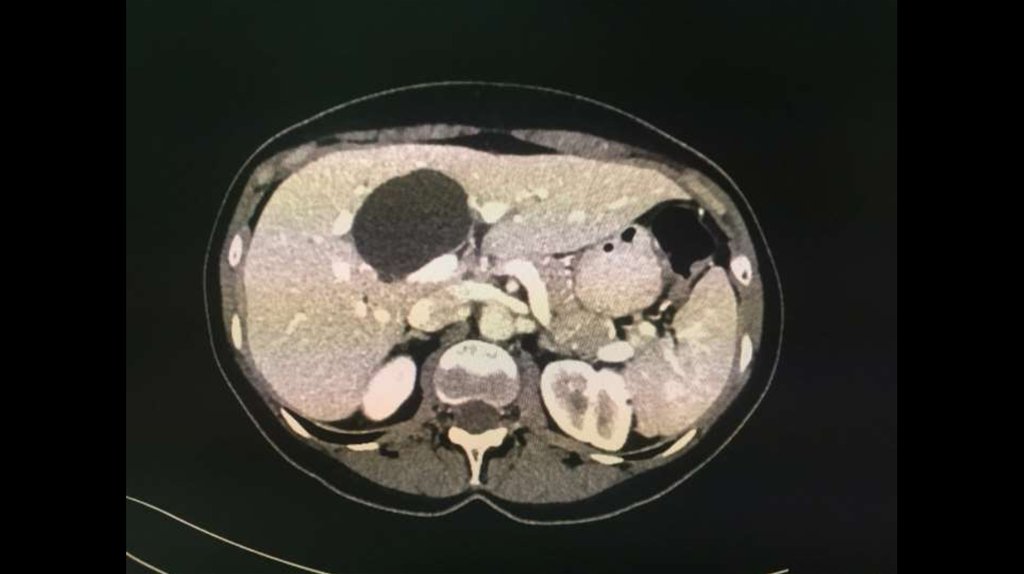

По направлению из ЦГБ в ККБ №1 поступил пациент М., 48 лет, с диагнозом «Эхинококкоз

печени»

Пациенту в плановом порядке выполнено КТ ОБП. По результатам исследования выявлена

эхинококковая киста IV-V сегментов.